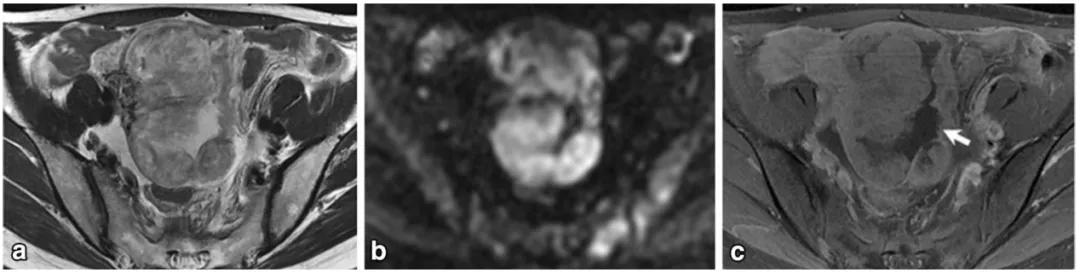

女,22 岁,无性细胞瘤。乳酸脱氢酶及碱性磷酸酶升高。T2WI 示右侧卵巢分叶状肿物(图 a),DWI 呈高信号(图 b),增强扫描明显强化(图 c)。箭头显示肿物内可见纤维血管分隔。